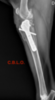

¿QUE ES LA DISPLASIA DE CODO?

La displasia de codo (DC) es una enfermedad hereditaria del desarrollo de las codos, es decir, los animales nacen con codos normales y a medida que crecen, se va desarrollando la DC. Al igual que la Displasia de cadera, se trata de una patología poligénica (inducida por varios genes, no por uno sólo, por eso es tan difícil de erradicar).

Afecta generalmente a perros de razas grandes ( Labrador, Golden Retriever, Pastor Alemán, Boyero de Berna, Terranova,